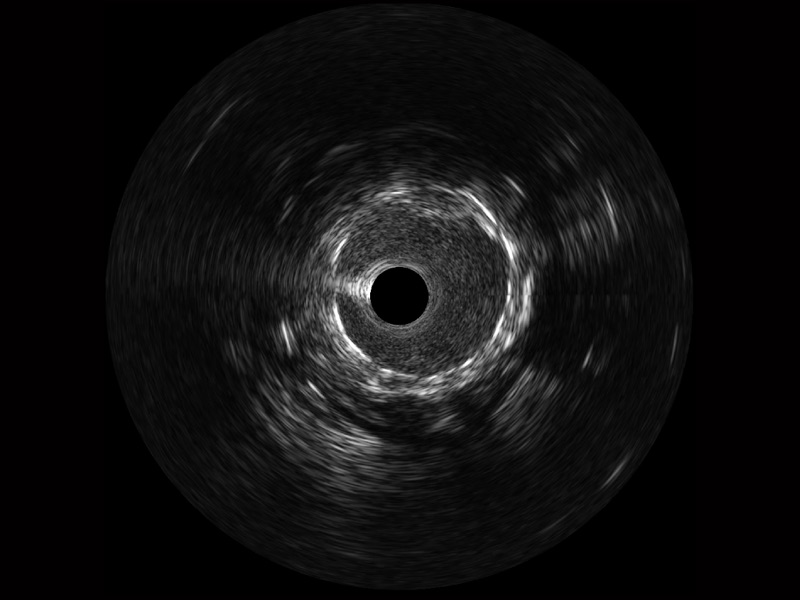

• 传统IVUS图像

对比传统IVUS导管成像,米兰官方网站宽频IVUS图像的近场支架梁显影更细腻,远场中膜外血管仍清晰可辨,兼顾远中近,兼顾分辨力与穿透深度